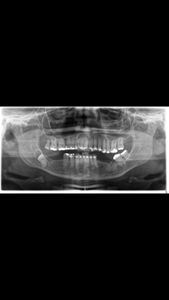

Com o valor arrecadado, vou fazee a cirurgia pra retirar o cisto e o dente siso, vou implatar os dentes que falta que são da arcada inferior, como mostra a radiografia panoramica, tbm vou fazer a manutenção do aparelho ortodontico, pois desde a pandemia que não faço a manutenção.